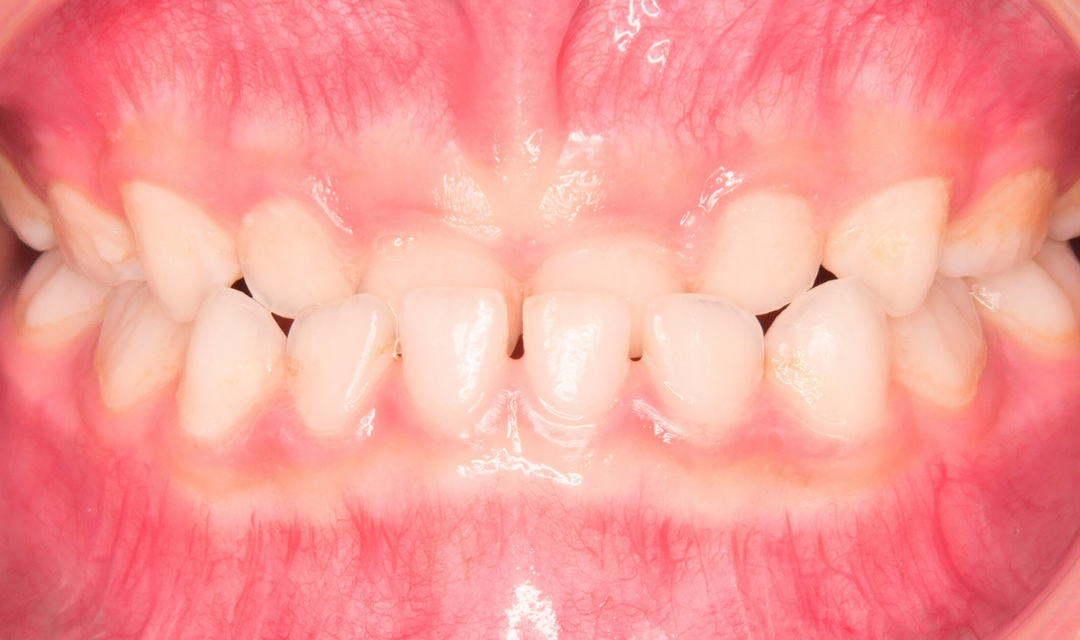

初診時の状態

初診時には、前歯の噛み合わせとお口の使い方に特徴が見られました。小さい時は指しゃぶりをしていましたが、最近はもうしていないとのことでした。

前歯が上下逆に噛み合う反対咬合(下の前歯が上の前歯より前に出ている状態)でした。